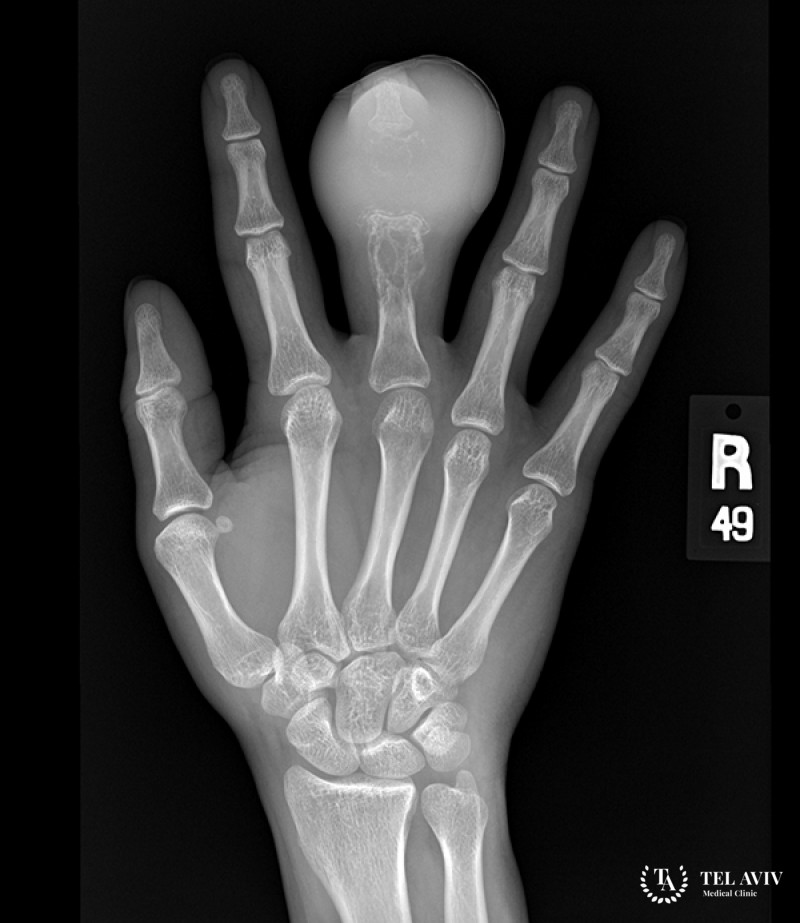

- Рентгенографического исследования пораженных участков с разной проекцией;